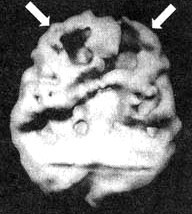

Раньше СДВ рассматривали как некоторое нарушение, имевшееся у гиперактивных мальчишек и компенсировавшееся по мере того, как они взрослели. Сегодня мы знаем, что многие, страдающие СДВ, с возрастом не избавляются от этих симптомов и что это нарушение часто встречается не только у представителей мужского пола, но и у девочек и женщин. По некоторым подсчетам, в США численность страдающих СДВ доходит до 17 млн человек. Кент Когда мы познакомились, ему было 24 года. Он обратился за помощью, так как к тому времени три года просидел на первом курсе колледжа. Он не мог сдать экзамены за первый курс. Он хотел поступать на медицинский факультет университета. Все говорили ему, что он «рехнулся»! Как он мог рассчитывать поступить на медицинский факультет, если был не в состоянии сдать экзамен за первый курс колледжа? Однако потом его мать прочла книгу под названием «Окна в сознание с СДВ» и подумала, не с этой ли проблемой столкнулся ее сын. Ознакомившись с историей болезни Кента, я понял, что мы имеем дело с врожденным и недиагностированным случаем СДВ. Еще в детском саду он не мог долго сидеть на месте; он был беспокойным, отвлекающимся, неорганизованным и потому за ним закрепилась репутация неудачника. Отец Кента предложил провести ему сканирование SPECT. Он хотел убедиться в том, что Кент не пытается найти очередной отговорки, которая объясняла бы отсутствие результатов. В состоянии покоя мозг Кента работал нормально. Однако как только Кент постарался сосредоточиться, префронтальная кора «отключилась». Получив результаты клинического исследования и SPECT, я назначил Кенту Adderall, лекарственный стимулятор для лечения симптомов СДВ. Результаты оказались блестящими. В течение следующего семестра он сдал все долги. Через полтора года получил диплом Associate of Arts (ученая степень, которая присваивается по завершении двухлетней программы обучения), а еще через три года получил степень бакалавра по биологии. Он поступил на медицинский факультет! Через несколько месяцев приема Adderall я сделал Кенту повторное сканирование SPECT. Как было видно на снимке, реакция на лечение была не просто положительной: после приема препарата активность его префронтальной коры заметно усилилась. Мозг Кента. СДВ. До и во время приема Adderall Трехмерное изображение — нижняя поверхность. ![]() В состоянии покоя — обратите внимание на хорошую активность всего мозга. ![]() Во время концентрации: обратите внимание на выраженное снижение активности в префронтальной коре (см. стрелки). ![]() При концентрации во время приема Adderall — обратите внимание на улучшившуюся активность в мозге в целом. Отношение к Кенту со стороны его отца потрясающе изменилось. Он сказал мне: «Я всегда думал, что он просто ленится. Так грустно думать, что все эти годы он был нездоров, а я просто ругал его за лень. Как же мне хотелось бы вернуть это время назад!» У меня был пациент, владевший 10 компаниями, — ему это было необходимо, чтобы оставаться «в тонусе». Когда мозг работает на «сниженных оборотах», человек чувствует себя некомфортно. Подсознательно такие люди стремятся «завести» свой мозг кофе или сигаретами (и то, и другое — мягкие стимуляторы), ссорами, гневом, быстрым темпом жизни или физической активностью с мощным стимулирующим эффектом, как, например, банджи-джампинг (любителям этого вида развлечений стоит пройти сканирование мозга по поводу СДВ!). СДВ в семье По мнению специалистов, на развитие многих психических нарушений большое влияние оказывает наследственность. Не является исключением и СДВ. Вот история болезни, прослеживающаяся в одной семье. Пол (20 лет) пришел ко мне на прием, так как не мог окончить учебу на последнем курсе колледжа. В классе ему было трудно писать контрольные работы, он не мог сконцентрироваться, а мотивация находилась на довольно низкой отметке. Он стал подумывать о том, чтобы бросить школу и идти работать вместе с отцом. При этом ему совсем не нравилась перспектива бросать учебу за несколько недель до выпуска. Пока я заполнял его историю болезни, Пол успел рассказать мне о том, что раньше у него случались приступы депрессии, которые ему лечили лекарством Prozac без особого успеха. Сканирование SPECT выявило повышенную активность лимбической области (связанную с депрессией) и пониженную активность ПК во время выполнения задания на концентрацию. Я назначил лечение антидепрессантами в сочетании с лекарственными стимуляторами. Результат оказался прекрасным. Он окончил колледж и получил работу, о которой мечтал. Увидев, как помогло лечение ее сыну, мать Пола Пэм пришла ко мне на прием сама. В детстве ей трудно давалось учение. Несмотря на то что она была очень артистичной, ей не особо хотелось учиться, и учителя поставили на ней крест. Уже став взрослой, Пэм вернулась к учебе и получила диплом учительницы начальных классов. Чтобы преподавать в средней школе, ей надо было сдать национальный экзамен для учителей. Все четыре попытки оказались неудачными. Пэм была готова отказаться от этой затеи и пойти учиться по другой специальности, но тут она увидела, как помогло лечение Полу. И тогда она подумала, что, может быть, и ей можно помочь. Ее результаты SPECT были сильно похожи на результаты Пола. Ей было назначено похожее лечение, и через четыре месяца она сдала свой экзамен. После того как в семье появилось два успешно пролеченных случая, Пэм привела ко мне девушку-тинейджера Карен. Как и ее брат, Карен была умным ребенком. Тем не менее ей плохо давалась учеба. К тому времени, как мы встретились, она жила в Лос-Анджелесе и занималась на факультете журналистики. Она жаловалась, что учебный материал для нее слишком труден. Она часто страдала от плохого настроения, беспокойства, легко отвлекалась, была импульсивна и вспыльчива. Несколько лет назад она лечилась от алкоголизма и привыкания к амфетамину. Она рассказала, что алкоголь снимал у нее беспокойство, а амфетамин помогал сосредоточиваться. Результаты SPECT-сканирования у Карен оказались похожи на результаты ее матери и брата. Как только она начала принимать лекарства, в ее состоянии произошли перемены, которым она была очень рада. В классе она могла спокойно сосредоточиться, а задания стала выполнять в два раза быстрее. Уверенность в собственных силах укрепилась настолько, что Карен стала искать работу ведущей в телепрограмме. Раньше ей это даже не пришло бы в голову. Из всех членов семьи с самым сильным нежеланием пришел ко мне их отец — Тим. Он упирался, несмотря на то что и Пол, и Пэм, и Карен говорили ему, что он должен пойти. Он говорил: «Со мной все нормально. Посмотрите, какого успеха я сумел добиться!» Однако в его семье знали и другое. Несмотря на то что Тиму на самом деле принадлежал продуктовый магазин, сам он был замкнутым и отстраненным. Он быстро уставал, легко отвлекался и был довольно разбросанным в работе. Успеха в бизнесе он добился во многом благодаря сильной команде сотрудников, которые и занимались реализацией его идей. Ему было трудно учиться новым играм, например карточным, поэтому он стремился избегать каких-то встреч и общественных мероприятий. Тиму нравились острые ощущения. Например, несмотря на то что ему было уже 45 лет, он любил кататься на мотоцикле. В школе, в последних классах он учился плохо. Несмотря на высокий IQ, с трудом окончил колледж. Он менял одну работу за другой, пока не скопил достаточно денег на то, чтобы купить продуктовый магазин. В конце концов Пэм удалось уговорить Тима пойти ко мне на прием. Сама она уже собиралась с ним разводиться, так как была убеждена, что он ее не любит. Позже он рассказывал мне, что тогда чувствовал себя совершенно опустошенным и эмоционально, и физически, чтобы проводить с ней значительную часть времени. |